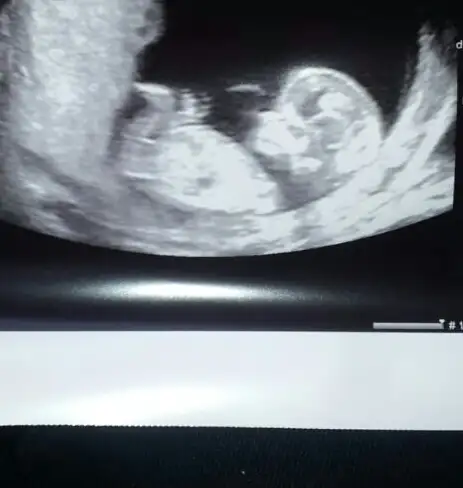

Hmm .. paralel gercekten :)işte resmi.çok tatlı.burda 13 haftalıktı.eli bile belli oluyor :)

Erkek gibi geldi banaAnlayan arjadaslar benim icin arkadasimin bebisi bi yorumlasin herkes ?? 12 +3 bekluyorum ...